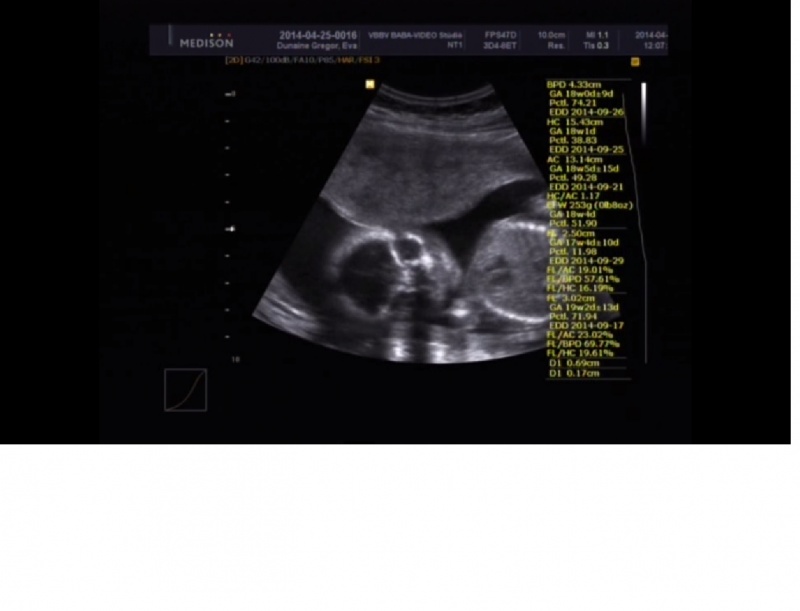

Ép agy és arckoponya ábrázolódik. A koponya alakja, csontosodása normális. Normál tágasságú liquorterek. (agykamra)

Arc: ajakhasadék nem észlelhető. Orbita orrcsont megjelenése szabályos. Nyaki régió eltérés nélkül, a nyaki redő vastagsága kisebb mint 5 mm.

Szív: Normál tengelyállású. Alakja, nagysága, elhelyezkedése és a cardio-thoracicus index normáis. (szívelégtelenség kizárva). Szabályos négy üreg ábrázolódik. A kiáramlási pályák szabályos lefutásúak és egyelőek, egymást keresztezik. Kompenzált magzati keringés.